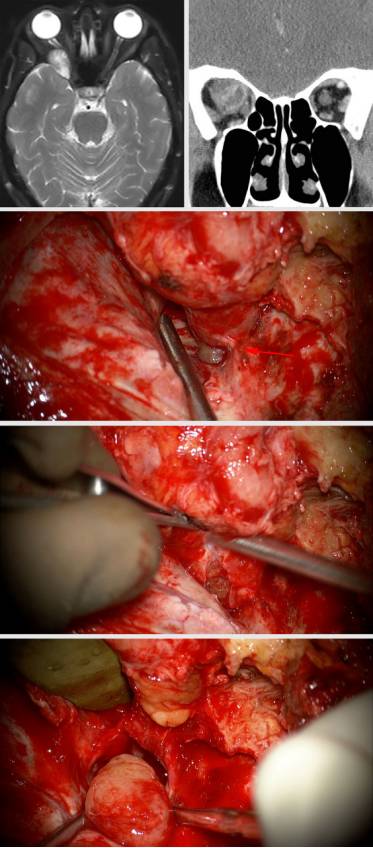

眶外侧入路(眶外侧壁切开术)

Kronlein于1889年首次描述了眼眶的侧方入路。1976年,Maroon和Kennerdell对切口进行改进并引入手术显微镜。改良后的切口形似曲棍球球棍,绕着外侧眉毛延伸至外眦后方的35-40mm处,不仅有效地避开了支配额肌的面神经,还能够处理上方、下方和外侧方的锥内型肿瘤。

沿皮肤切口从额颧复合体(frontozygomatic bone)的中点开始切开颞肌筋膜,颞肌牵向后方以暴露眶外侧壁,再弧形切开其表面的骨膜。随后在可弯小压肠板(malleable ribbon)的保护下从眶壁内面剥离眶筋膜。

使用不带护板的B1铣刀在颧额缝上方进行第一道截骨,这样可以使额颧复合体作为整体被卸下。随后在第一道下方1.5cm的地方截第二道,从而完成眶外侧壁切开。进一步用磨钻磨除部分蝶骨以暴露眶尖。

在外直肌下方或肿瘤的隆起部位切开眶筋膜,牵开外直肌以便更好地操作肿瘤包膜,切忌直接离断外直肌否则会导致瘢痕形成和眼球活动受限。余下的肿瘤切除过程与前文所述相同。

术后患者经常有复视出现,这个症状往往会在数周内消失。